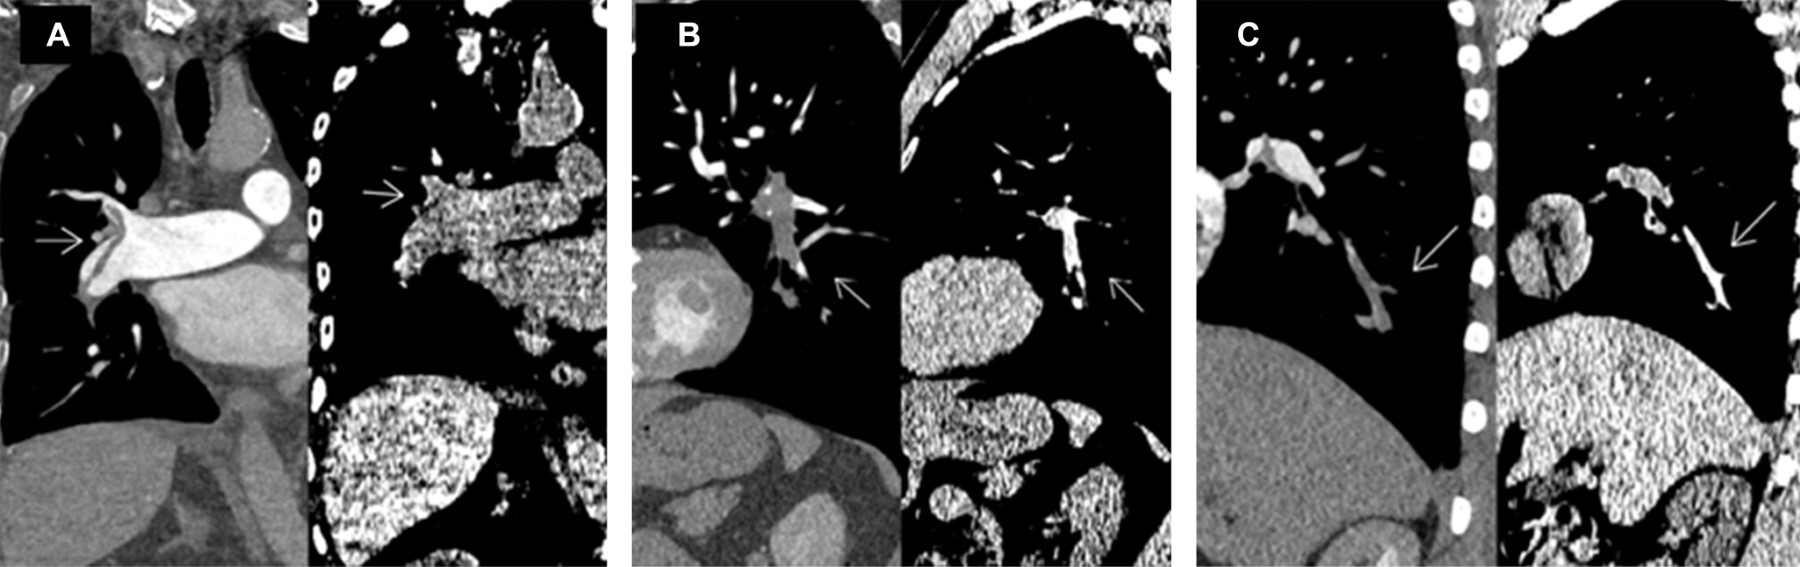

Se determinó asociación entre la trombosis pulmonar y la arteria segmentaria afectada, con resultados estadísticos significativos (p = 0.03), y OR de 4.33, IC95% 1.60-11.69; en consecuencia, el compromiso de la arteria segmentaria se considera un factor de riesgo para TEP. De la misma manera se evidenció la asociación entre la presencia del signo de vaso hiperdenso con el tipo de trombosis pulmonar (parcial o completa), con valor de p = 0.001, altamente significativo, y OR de 6, con IC95% 1.003-35.905), debido a lo cual, la presencia del signo de vaso hiperdenso, evidenciado mediante TC simple de tórax, es un factor de riesgo para desarrollar TEP (Tabla 1 y Figura 3).

Nuestros resultados muestran que por medio de la tomografía simple de tórax de pacientes con sospecha de TEP (posteriormente confirmada por angiotomografía), se logró visualizar con ventana cerebral estándar (W:80 L:40), el signo de vaso hiperdenso; además de una asociación entre la presencia de trombosis pulmonar con el compromiso de las arterias segmentarias.

Finalmente, se concluye que la probabilidad de trombosis pulmonar completa es seis veces mayor si se presenta el signo de vaso hiperdenso por TC simple de tórax con ventana cerebral estándar (W:80 L:40).